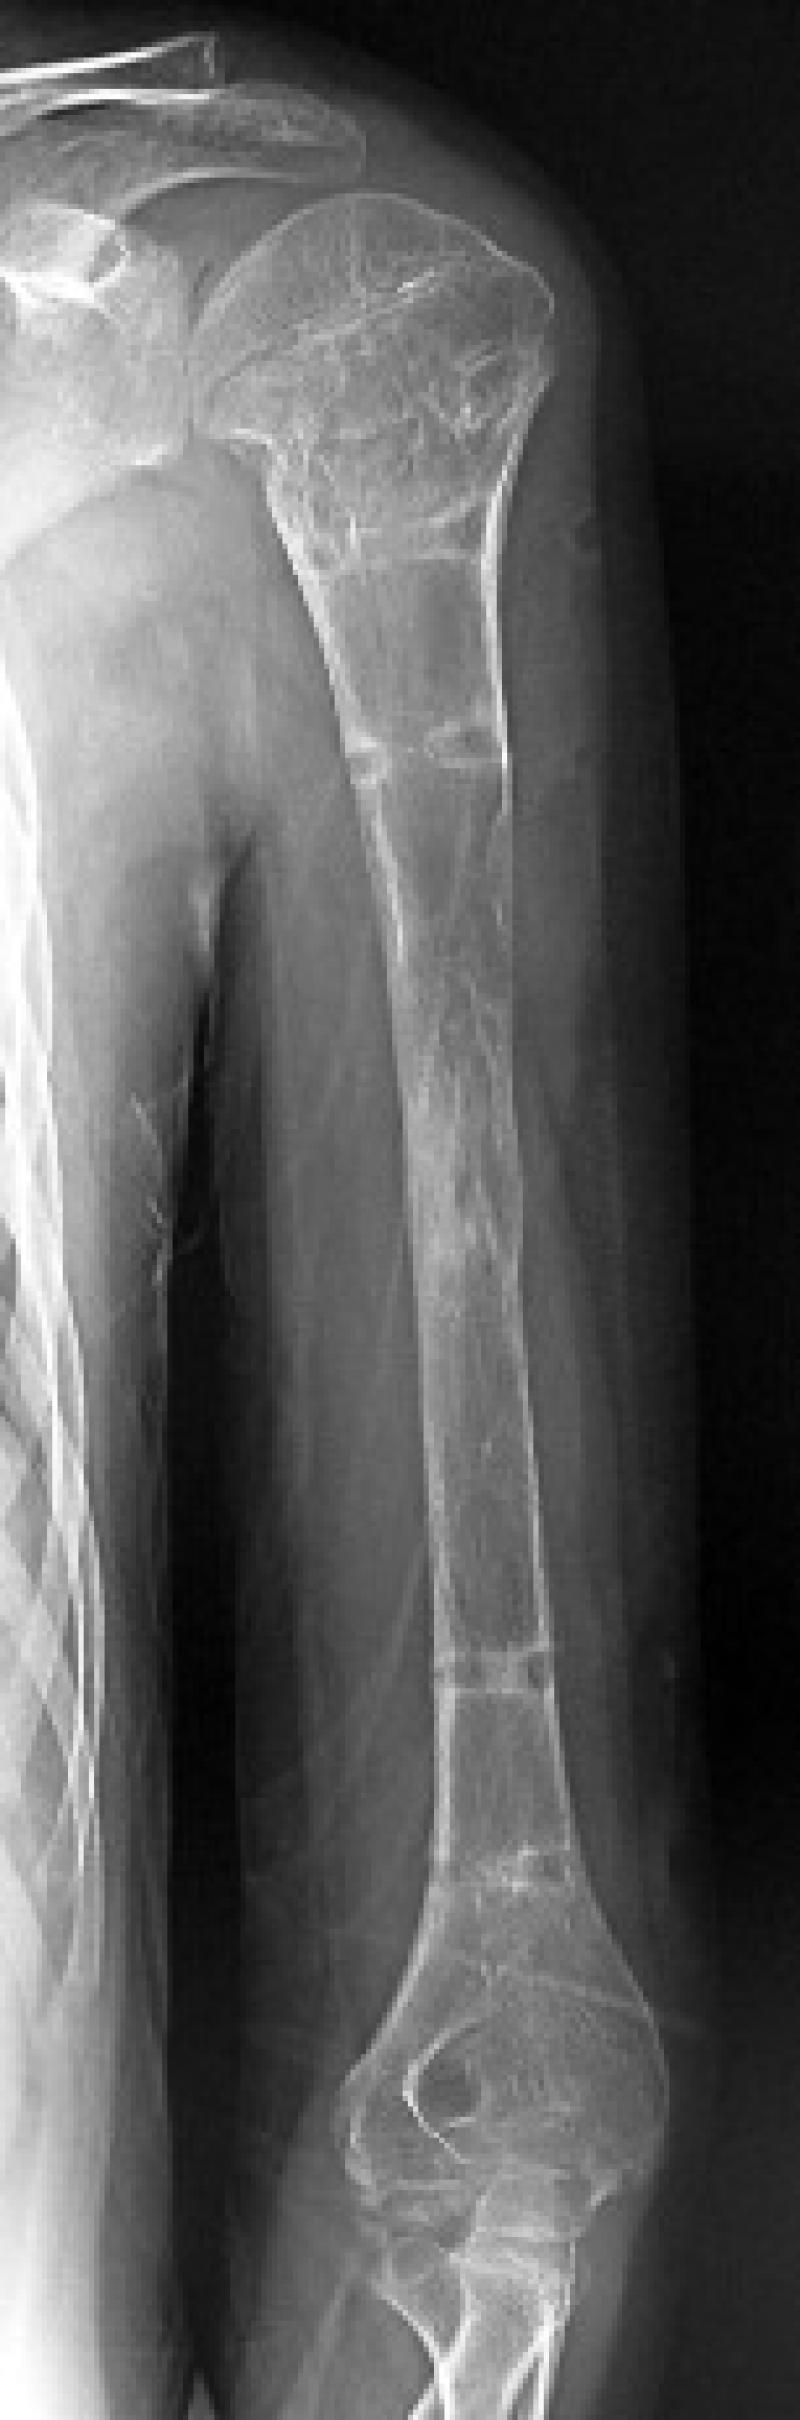

For lengthening surgery, the individual needs to be diagnosed with short stature first. To diagnose short stature, after examining patient history, physical examination and laboratory evaluations are made. In the physical examination stage, the length of arms and legs of patients between fixed points is measured and both standing and lying calculations are made. Also, special stature roentgens are used for millimetric measurements.

For length differences of more than 2 cm, surgical intervention is necessary. With lengthening surgery, which is an orthopaedic process, patient’s functional capabilities can be improved for lengthening. For children, the shorter side can be lengthened to equalise limb length and rarely, the growth of longer side can be slowed down.

In lengthening surgery, it is possible to grow 10-15 cm with one session. With sessions each requiring a different surgery, both lower and upper region of legs can be lengthened. Especially for children with dwarfism syndrome occurring from achondroplasia or hypocondroplasia, the first session lengthening should be performed between ages of 5 - 7.

While the surgery starting age is accepted as 7 in the classical literature, in some cases starting at ages 2 - 3 is also possible. 10 - 15 cm of growth in the first session of the surgery, 8 - 12 cm in the second session, and 8 - 10 cm in the third session can be provided. For body limbs to have a healthy ratio, arm lengthening surgery is performed between ages of 14 - 16 for 10-12 cm of growth. Since bones harden after 20 years of age, the first session is performed at ages of 5 - 7, second session at 10- 12, third session at 14-16 and lengthening process is completed.

After the lengthening surgery, height growth starts following the end of 7-10 days of recovery period. An average of 5cm of lengthening is provided for legs with 1mm lengthening per day for two months. According to the used technique, the lengthening time for 1cm can change between 1.5-2 months, and 4-6 for 5cm.